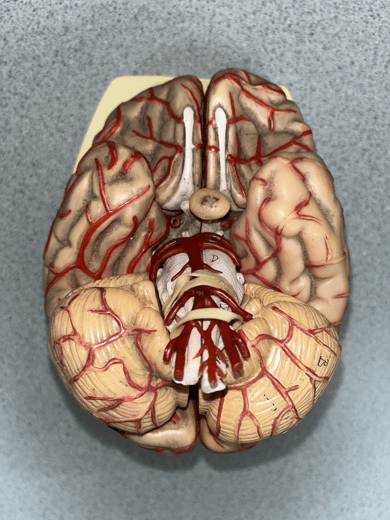

anterior cerebral artery

• An artery of the cerebral circulation.

• Originates from the internal carotid artery.

• Supplies the frontal and parietal lobes of the brain.

• Originates from the internal carotid artery.

• Supplies the frontal and parietal lobes of the brain.

posterior communicating artery

• An artery of the cerebral circulation (not shown).

• Connects the posterior cerebral and internal carotid arteries.

• Connects the posterior cerebral and internal carotid arteries.

posterior cerebral artery

• An artery of the cerebral circulation.

• Originates from the basilar artery.

• Supplies the temporal and occipital lobes, midbrain, and thalamus.

• Originates from the basilar artery.

• Supplies the temporal and occipital lobes, midbrain, and thalamus.

middle cerebral artery

• An artery of the cerebral circulation (not shown).

• Originates from the internal carotid arteries.

• Supplies the frontal, temporal, and parietal lobes.

• Originates from the internal carotid arteries.

• Supplies the frontal, temporal, and parietal lobes.

basilar artery

• An artery of the cerebral circulation.

• Originates from the convergence of the vertebral arteries.

• Supplies the cerebellum, pons, and inner ear through its branches.

• Originates from the convergence of the vertebral arteries.

• Supplies the cerebellum, pons, and inner ear through its branches.